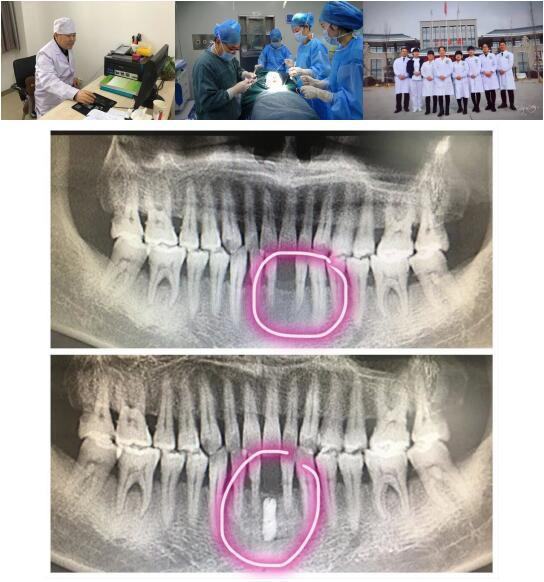

男同视频 高陵院区口腔科成功开展一例GBR引导骨再生技术种植牙